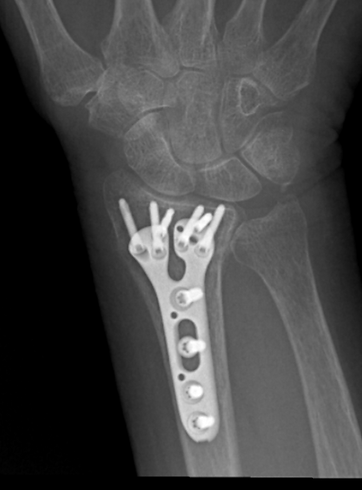

Most plates and screws stay in permanently. They're made from materials that your body accepts well. Removal is only needed if they cause problems, which is rare.

Living with Hardware

Most patients adapt quickly to having plates and screws in their wrist. The hardware becomes part of you, like a dental filling. You might feel it if you press on the area, but it rarely interferes with daily activities.

Cold weather in Durango sometimes makes the hardware feel different, but this doesn't mean anything is wrong. Your wrist may feel stiff on very cold mornings, but movement quickly warms things up. Occasionally, a tendonitis can develop, and if so, you should discuss this with Doctor Butzen, to avoid a tendon injury, necessitating tendon repair surgery.